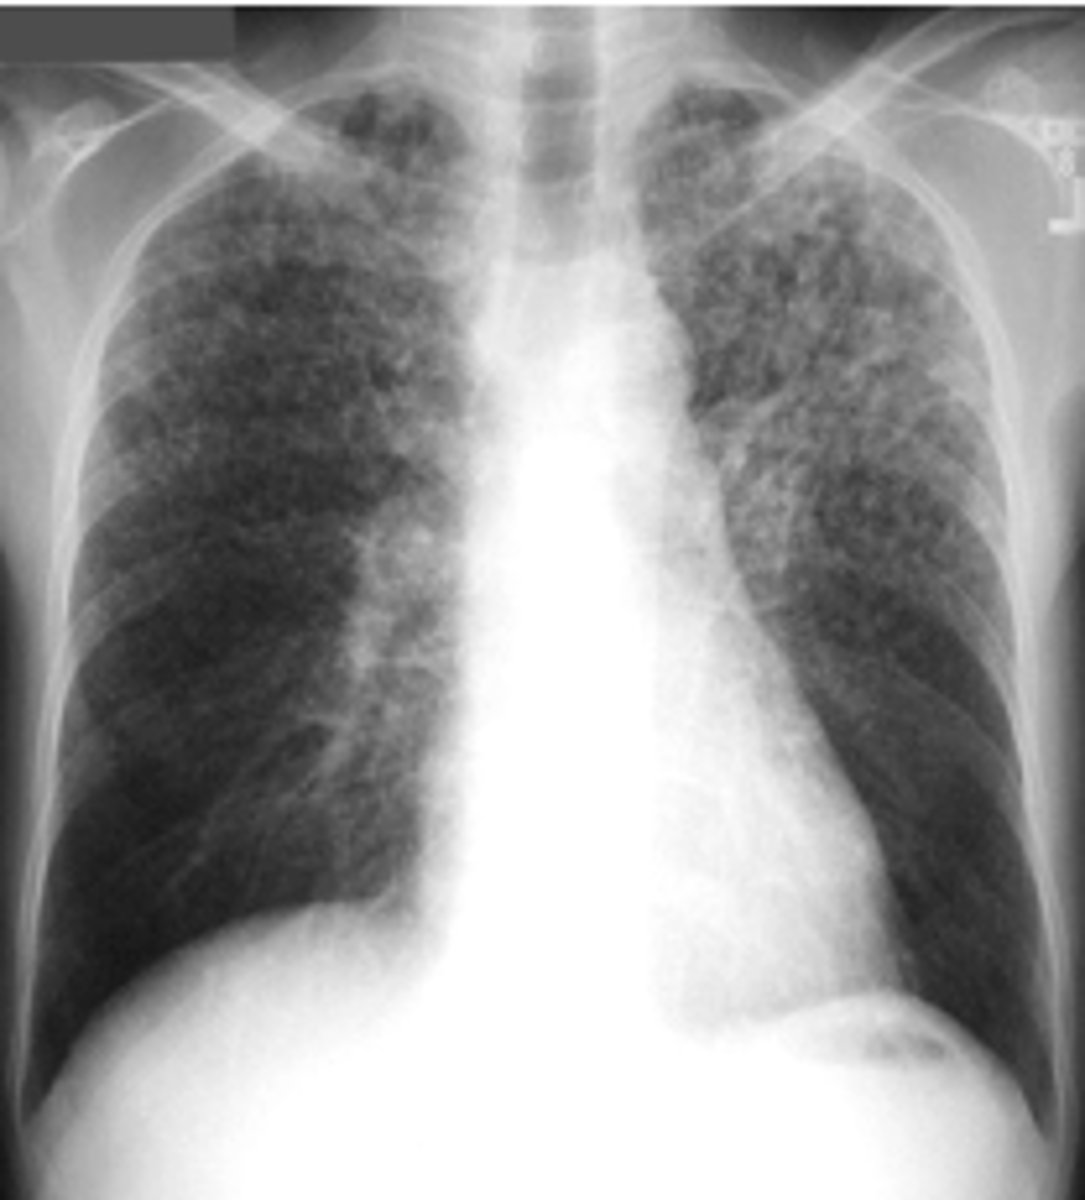

What is the pattern on the image of the back of the card?

Cystic PJP - PA chest radiograph shows diffuse bilateral reticulonodular interstitial infiltrates

<p>Cystic PJP - PA chest radiograph shows diffuse bilateral reticulonodular interstitial infiltrates</p>